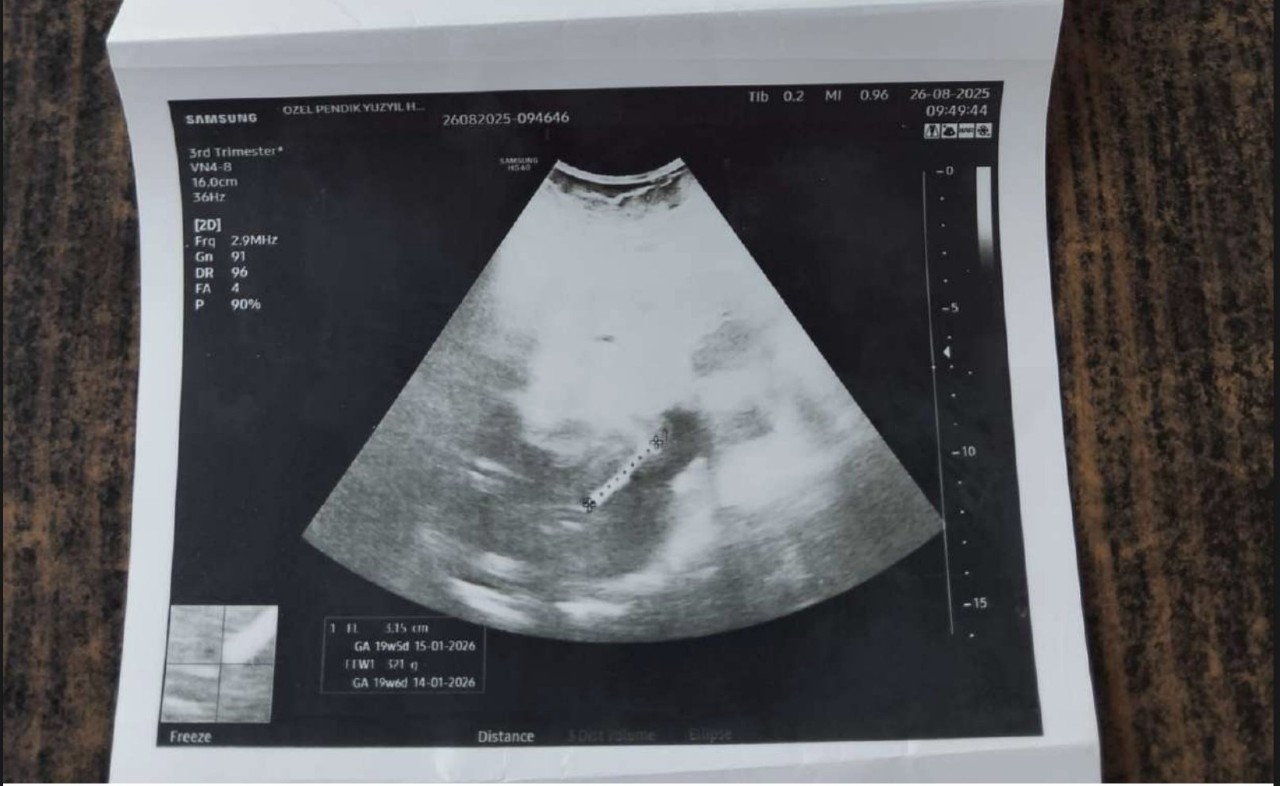

Omarova şu anda 8 aylık hamile ve resmi raporlu göbek fıtığı (umbilikal herni), D vitamini eksikliği, magnezyum eksikliği ve demir eksikliği sorunları sebebiyle tedavi görmekte.

Tüm bu tıbbi tabloya rağmen İstanbul İl Göç İdaresi’nin sınır dışı kararında ısrarcı olması, “doğumu geri gönderme merkezinde mi yaptırmayı planlıyorlar?” sorularını gündeme getiriyor.